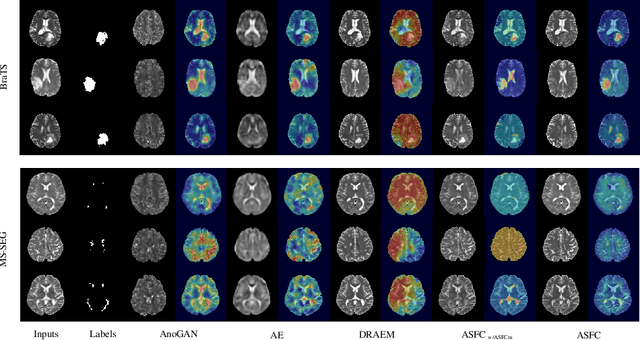

Abstract:Anomaly Detection (AD) on medical images enables a model to recognize any type of anomaly pattern without lesion-specific supervised learning. Data augmentation based methods construct pseudo-healthy images by "pasting" fake lesions on real healthy ones, and a network is trained to predict healthy images in a supervised manner. The lesion can be found by difference between the unhealthy input and pseudo-healthy output. However, using only manually designed fake lesions fail to approximate to irregular real lesions, hence limiting the model generalization. We assume by exploring the intrinsic data property within images, we can distinguish previously unseen lesions from healthy regions in an unhealthy image. In this study, we propose an Adaptive Fourier Space Compression (AFSC) module to distill healthy feature for AD. The compression of both magnitude and phase in frequency domain addresses the hyper intensity and diverse position of lesions. Experimental results on the BraTS and MS-SEG datasets demonstrate an AFSC baseline is able to produce promising detection results, and an AFSC module can be effectively embedded into existing AD methods.